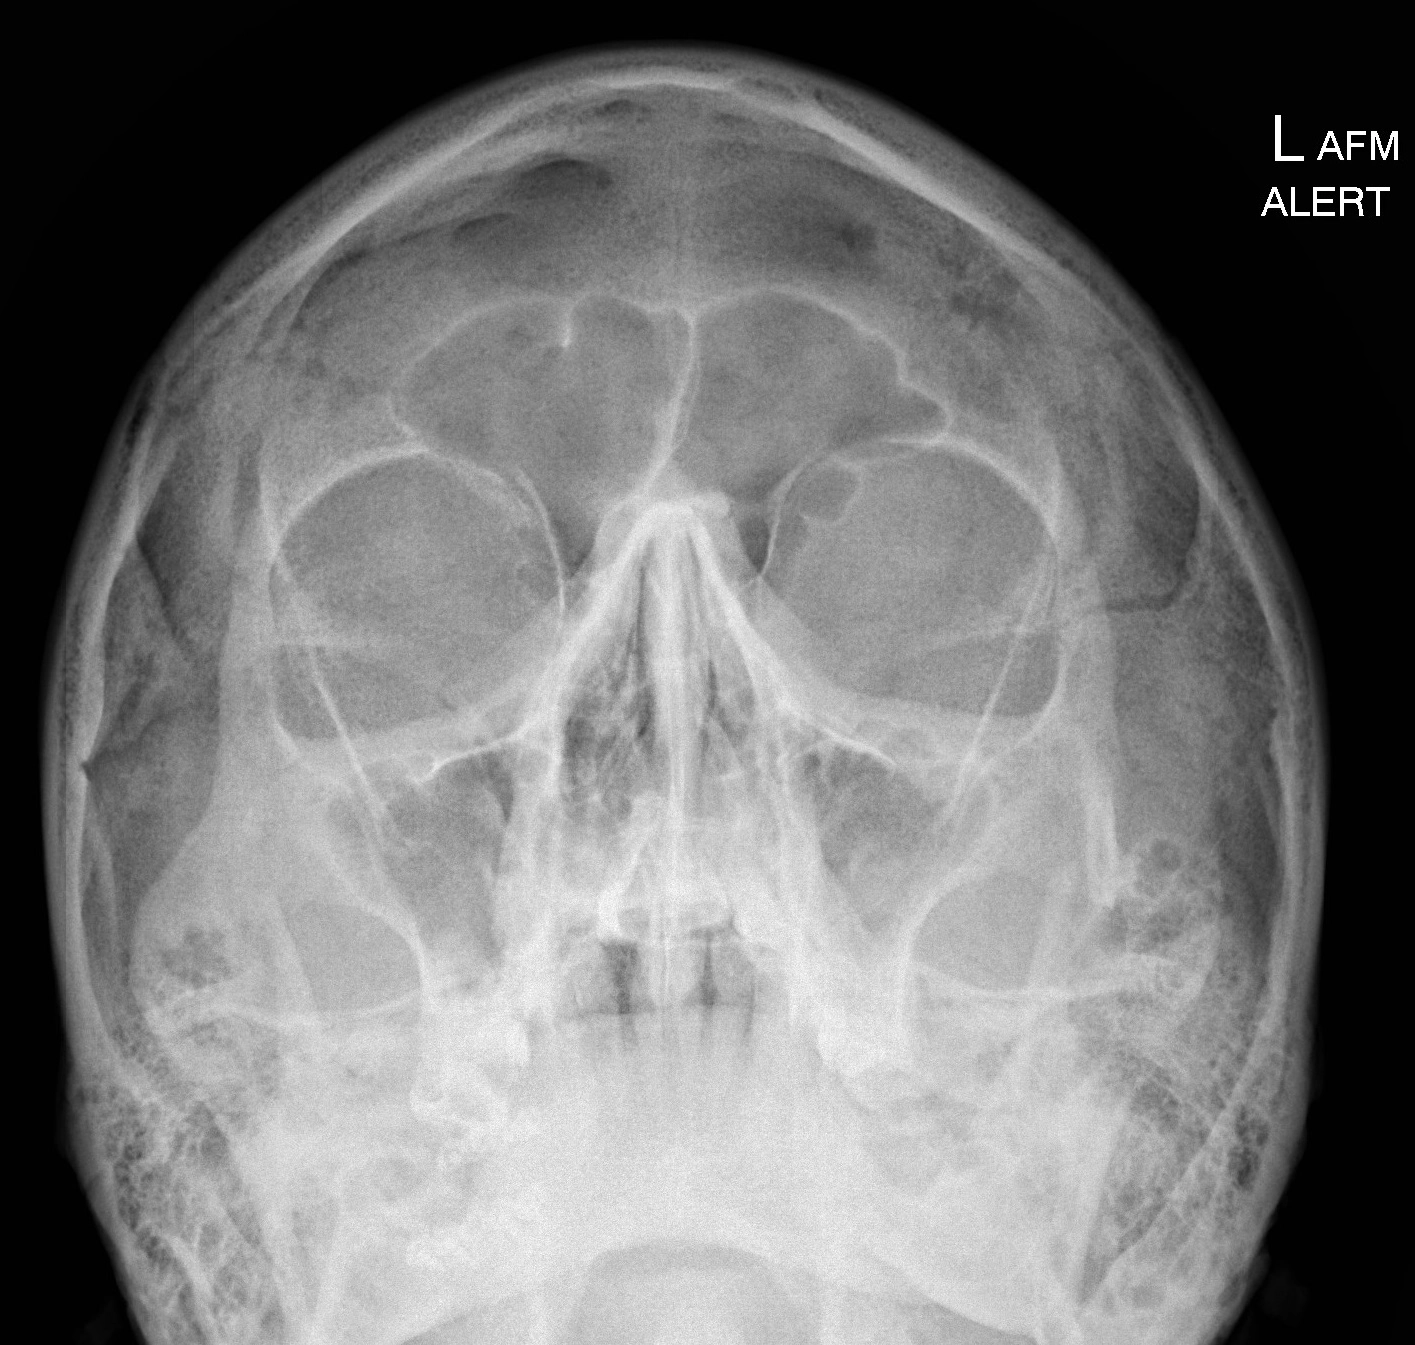

• Chấn thương hàm mặt

• Gãy xương đơn giản